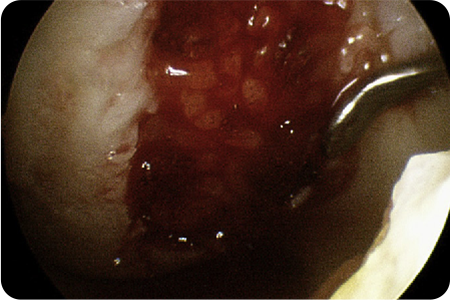

환자 자신의 골수에서 나온 줄기세포를 손상된 연골에 이식하여

연골을 재생시키는 치료법입니다. 손상된 연골에 미세한 구멍을 뚫어

골수 줄기세포가 나오게 한 후, 이 부위에 채취한 연골 일부를 갈아서

다시 이식합니다.